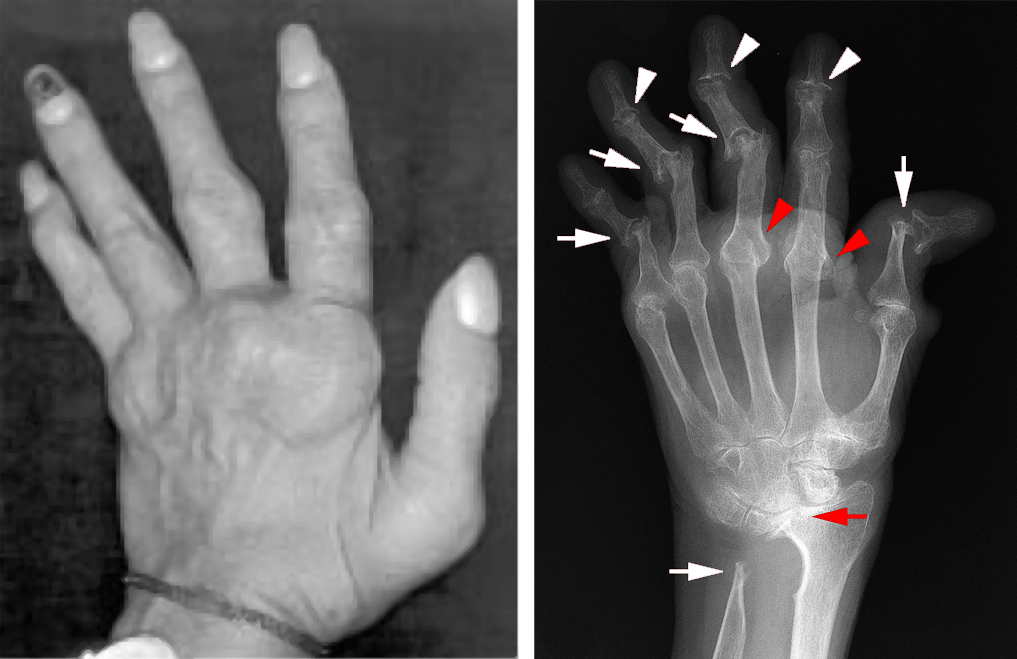

Advanced Rheumatoid Arthritis

As RA progresses, damage to cartilage and the ligaments supporting the joints can cause deformity. (Right) This X-ray shows an advanced case of RA, with dislocation and destruction of the joints.

Reproduced from (Left) Armstrong AD, Hubbard MC eds: Essentials of Musculoskeletal Care, ed 5. Rosemont, IL, American Academy of Orthopaedic Surgeons, 2015, p. 48. (Right) Johnson TR, Steinbach LS, eds: Essentials of Musculoskeletal Imaging. Rosemont, IL, American Academy of Orthopaedic Surgeons, 2004, p 394.